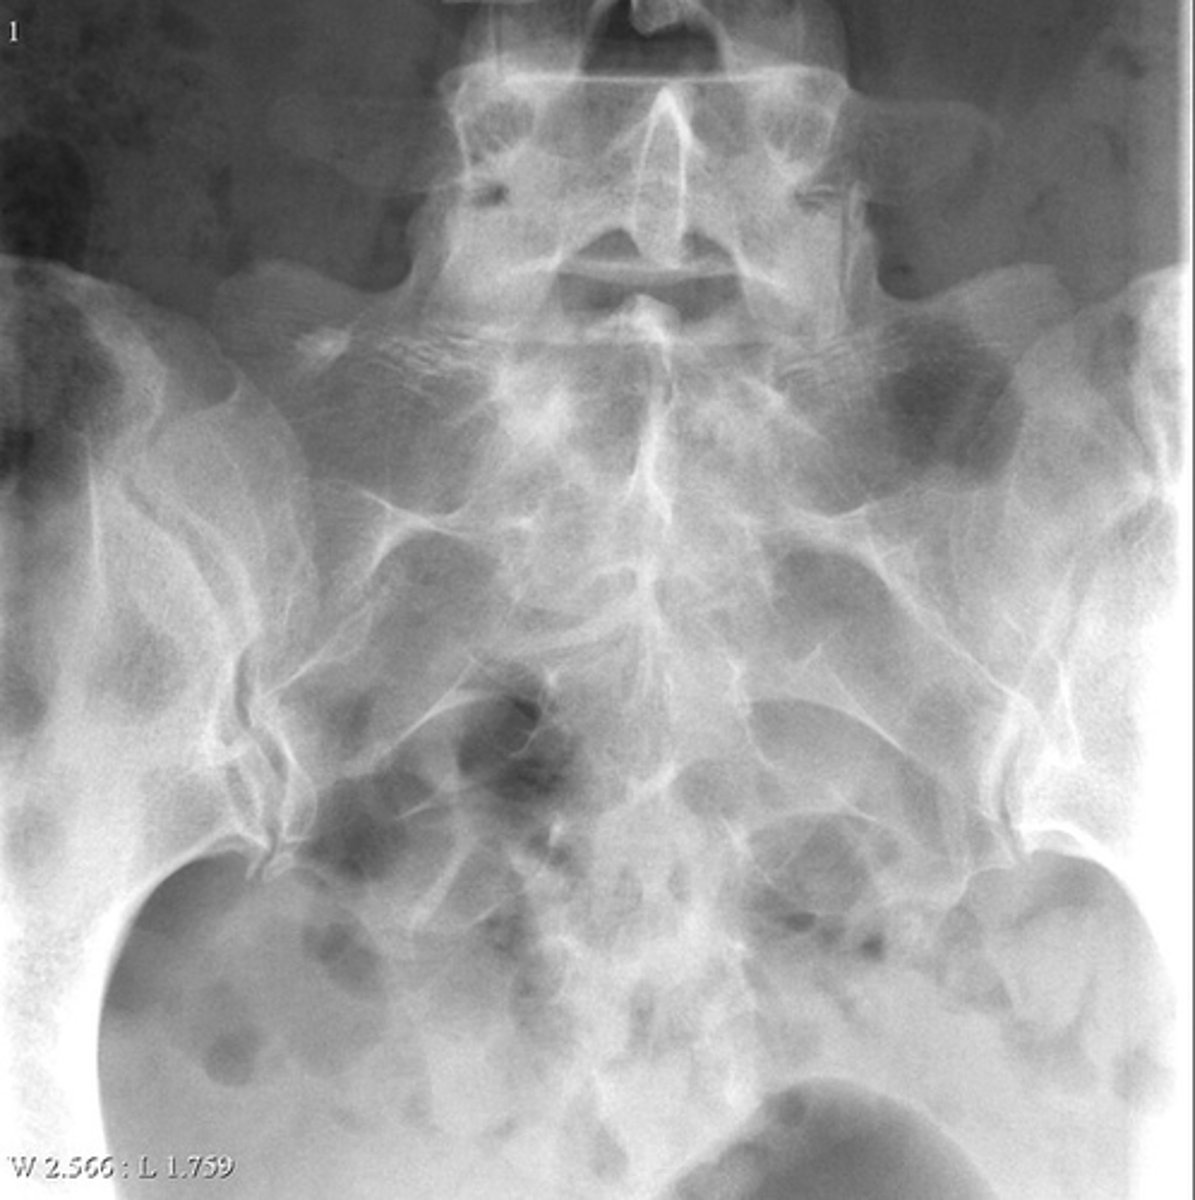

Lateral proximal tibia

Bone

<p>Bone</p>

- Longitudinal: epiphysis/metaphysis (up to joint surface)

- Eccentricity: eccentric

- Transverse: medullary

Location

- Lytic

- Geographic

- Short zone of transition

Behavior

<p>Behavior</p>

Cortex

<p>Cortex</p>

7

New cards

Nothing visible

Matrix

<p>Matrix</p>

8

None

Periosteal reaction

<p>Periosteal reaction</p>

9

Soft tissue swelling

Soft tissue involvement

<p>Soft tissue involvement</p>

10

Joint surface involved

Joint involvement

<p>Joint involvement</p>

11

Giant cell tumor

Most likely diagnosis?

<p>Most likely diagnosis?</p>

12

Refer to orthopedist or oncologist

Next step?

<p>Next step?</p>

13

Could be aggressive (20%)

Concerns/complications?

<p>Concerns/complications?</p>